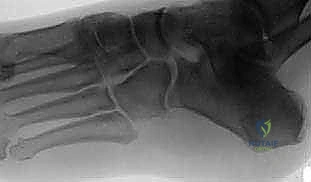

2. الأشعة السينية (X-Rays)

تعتبر الأشعة السينية الخطوة الأولى في التصوير. يتم أخذ وضعيات معينة للقدم (أمامية خلفية، جانبية، ومائلة).

* علامة آكل النمل (Anteater Sign): في الوضعية المائلة (Oblique view)، يمكن رؤية استطالة غير طبيعية في الجزء الأمامي من العظم العقبي، حيث يمتد ليلامس العظم الزورقي، ليأخذ شكل أنف حيوان آكل النمل. هذه العلامة الكلاسيكية تؤكد التشخيص في معظم الحالات.

![صورة توضح إدخال العضلة كفاصل بيولوجي](/media/hutaif_opertive/hutaif-ch49-calcaneonav